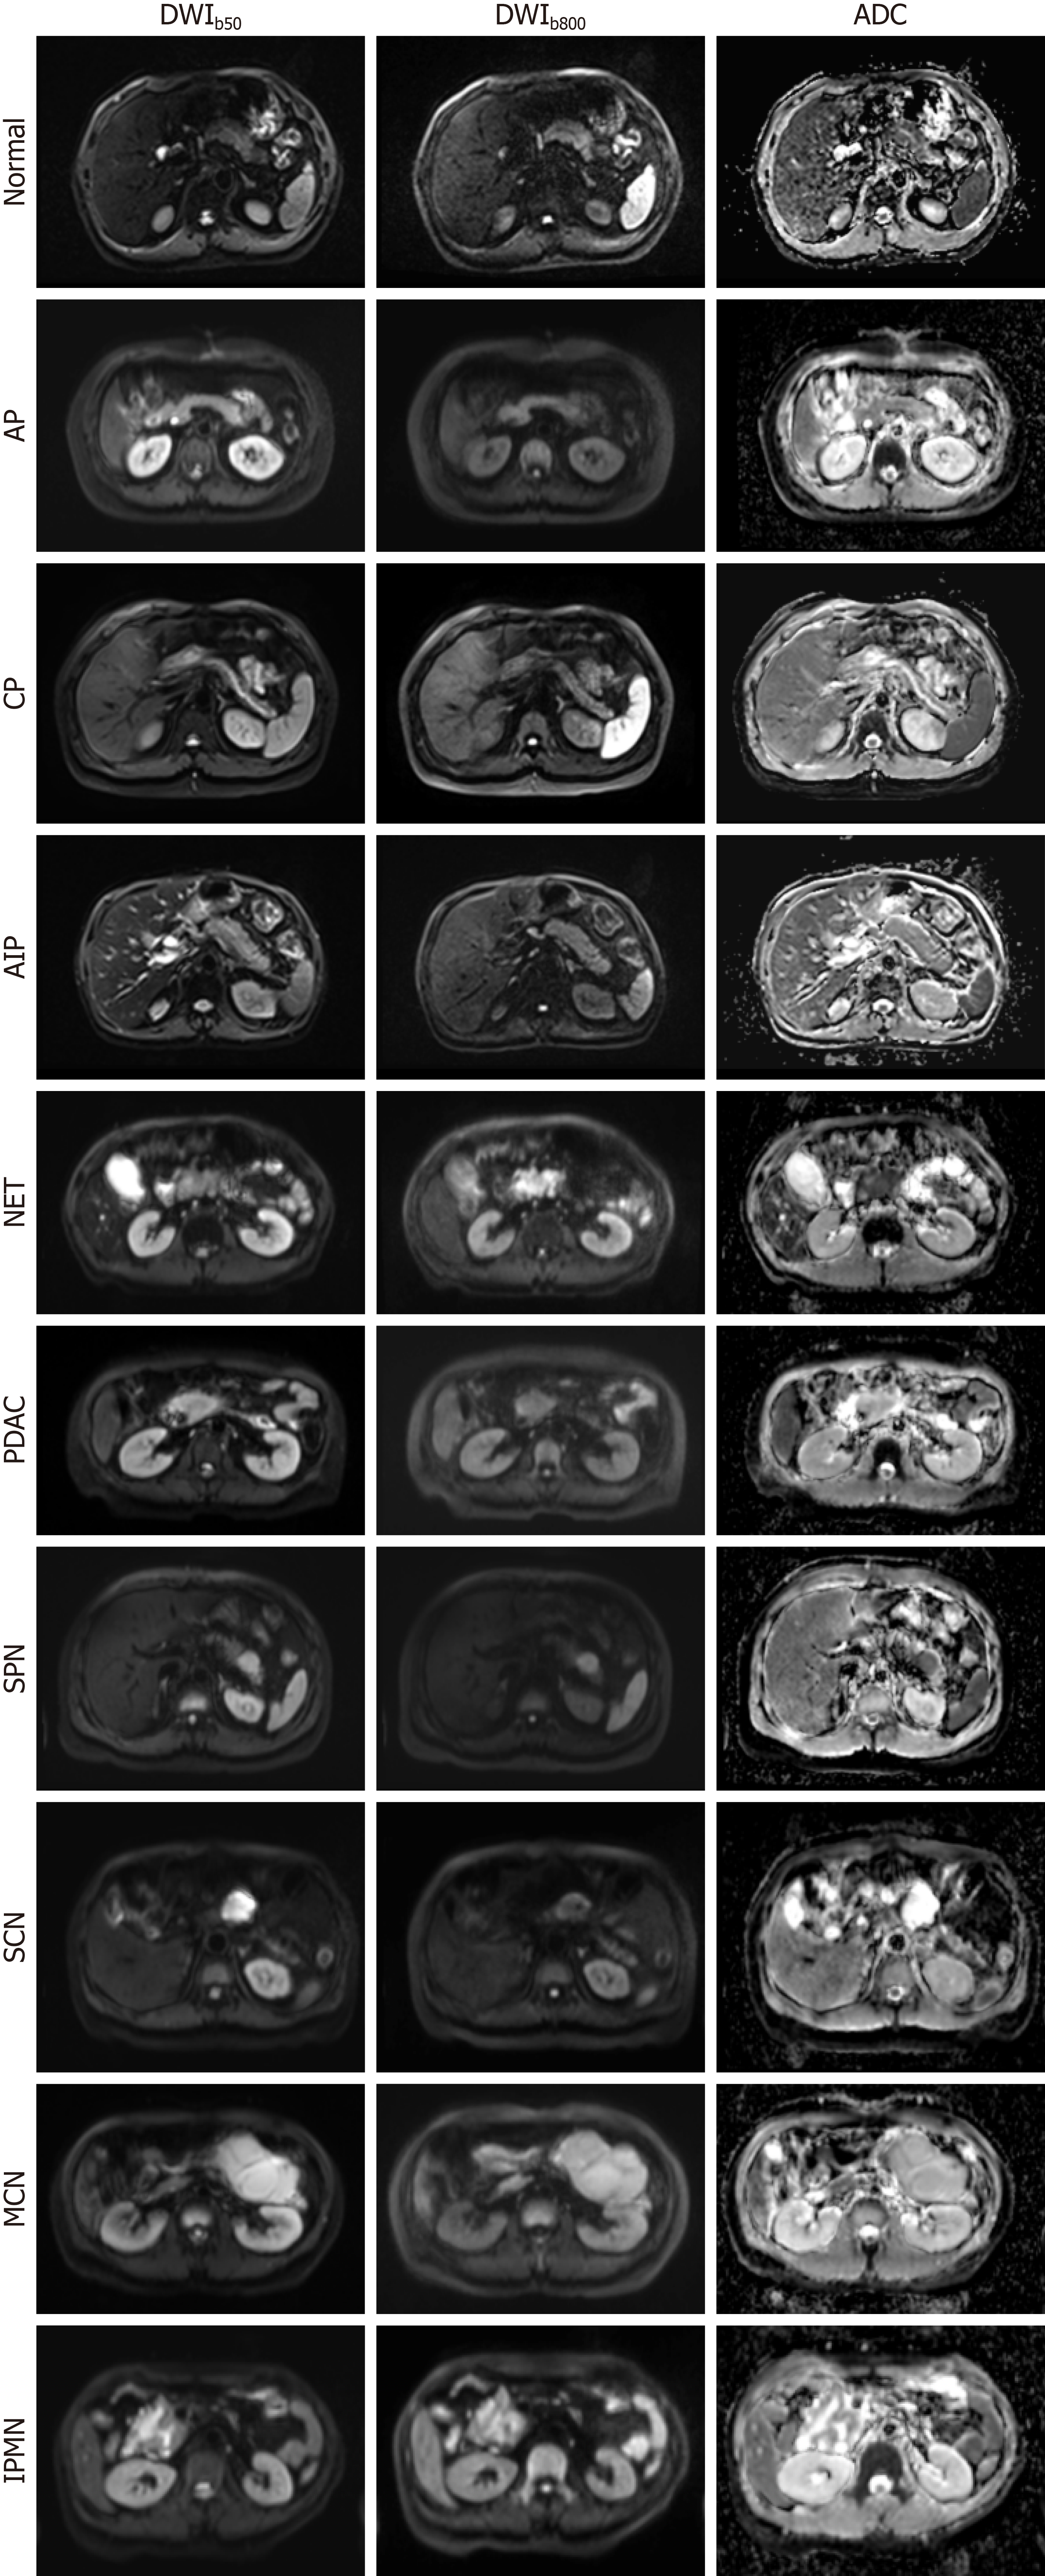

Figure 1 Diffusion-weighted imaging and corresponding apparent diffusion coefficient maps of the normal pancreas and nine repre sentative pancreatic pathologies, acquired on a 3.

0-T system with b-values of 50 and 800 s/mm2. AP: Acute pancreatitis; CP: Chronic pancreatitis; AIP: Autoimmune pancreatitis; NET: Neuroendocrine tumor; PDAC: Pancreatic ductal adenocarcinoma; SPN: Solid-pseudopapillary neoplasm; SCN: Serous cystic neoplasm; MCN: Mucinous cystic neoplasms; IPMN: Intraductal papillary mucinous neoplasm; DWI: Diffusion-weighted magnetic resonance imaging; ADC: Apparent diffusion coefficient.